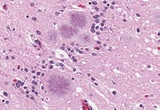

코돈129번 MM형의 문제

- 2012-03-25 22:03

- 양기화 의학박사

한국인은 광우병에 잘 걸리는 체질이다?

- 2012-03-17 19:43

- 양기화 의학박사

현지 언론에서 아레사 빈슨 사인을 CJD, vCJD로 의심한 이유

- 2012-02-19 18:17

- 양기화 의학박사

편향적으로 추정된 아레사 빈슨의 사인

- 2012-02-05 17:41

- 양기화 의학박사

급성 베르니케병으로 추정되는 아레사 빈슨의 사인

- 2012-01-28 22:09

- 양기화 의학박사

과학적으로 추정해본 아레사 빈슨 죽음의 원인

- 2012-01-28 21:18

- 양기화 의학박사

방송이 만들어낸 고(故) 아레사 빈슨의 사인

- 2012-01-14 22:56

- 양기화 의학박사

고(故) 아레사 빈슨양이 인간광우병으로 사망했다?

- 2012-01-14 22:56

- 양기화 의학박사